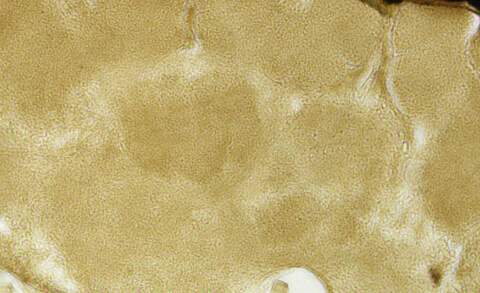

Èçͼ£¬ÃâÒß×黯ȾɫÉÕû¸öƬ×Ó¶¼ÊÇר»ÆÉ«£¬ÒõÐÔ¶ÔÕÕÈ´ÎÞ×ÅÉ«£¬ÇëÎÊÕâÊDZ³¾°»¹ÊÇÌØÒìÐÔ×ÅÉ«£¬ÈçºÎÅÐ¶Ï FU8SKMRU)RDWXX25SS@LT28.jpg SN8Z8UES([)$5630}M0ZVX3.jpg |